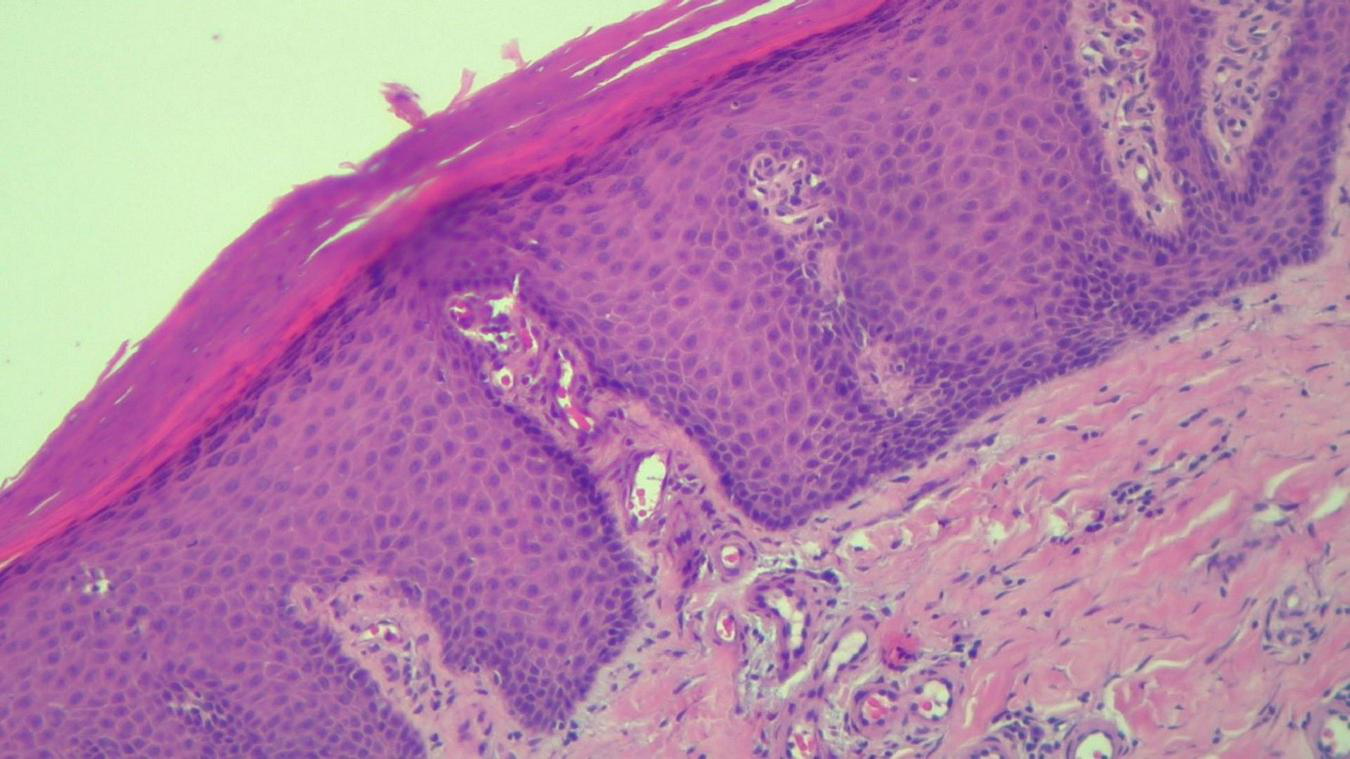

FIGURE 5

HEx100—Skin section showing marked hyper-parakeratosis with a granular layer of variable thickness, a regular, psoriasiform, acanthotic epidermis with tortuous capillaries in the superficial dermis and chronic inflammatory infiltrate.

The histopathological examination revealed (Figures 5–8). The examined skin fragment reveals an epidermis with marked hyperkeratosis, both ortho- and parakeratosis (confluent, with accumulations of neutrophils at this level—Munro microabscesses), a granular layer of variable thickness, with hypergranulosis and agranulosis, Kogoj pustules, regular psoriasiform acanthosis with elongated epidermal ridges, some rounded at the ends and fused at this level. The superficial dermis shows congested blood vessels, some with a tortuous appearance, and a perivascular inflammatory infiltrate consisting of lymphocytes, histiocytes, neutrophils (minimal), and extravasated red blood cells. Areas of erythrocyte exocytosis are also observed at the epidermal level.